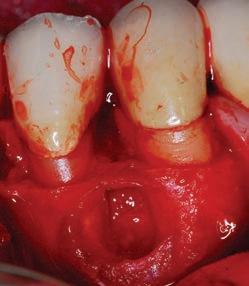

The third step of the treatment consisted of the crown lengthening, necessary to expose an adequate part of the root to obtain, after healing, the correct adhesion of the composite for the pre-prosthetic restoration and the successive prosthetic rehabilitation.

After the surgical flap elevation of the tissue and the bone remodeling, the flap was repositioned apically and sutured with a vertical mattress suture anchored in the periosteum (Figs. 5-6). The suture was removed after 7 days (Fig. 7).

glass fibre Figure 3: Root canal therapy completed under proper isolation. Figure 4: Radiography of completed root canal therapy and reconstruction made completely in glass hybrid cement. Figure 5: Clinical crown lengthening with a minimally invasive technique without mesial and distal discharges. Note the proximity of the reconstruction in glass hybrid material to the mesial bone ridge. Figure 6: Suture at the end of surgical therapy. It was left in place for 7 days Figure 7: Suture removal at 7 days. Post-surgical edema is still present.